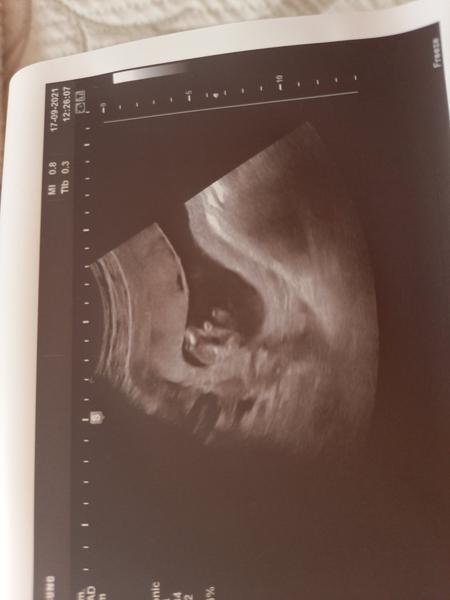

Ahoj holky,

tak dneska jsme byli na ultrazvuku v 20.tt. Bylo tam vidět tohle ...No paní doktorka nám řekla, že by zatím nedělala závěry, co to bude a že máme počkat.

Jasně, že počkáme na doktora, ale jsem strašně zvědavá. A hlavně...asi tam vidím pindíka 😁 Tak na to prosím taky koukněte, jestli jsem si to nevsugerovala 😁